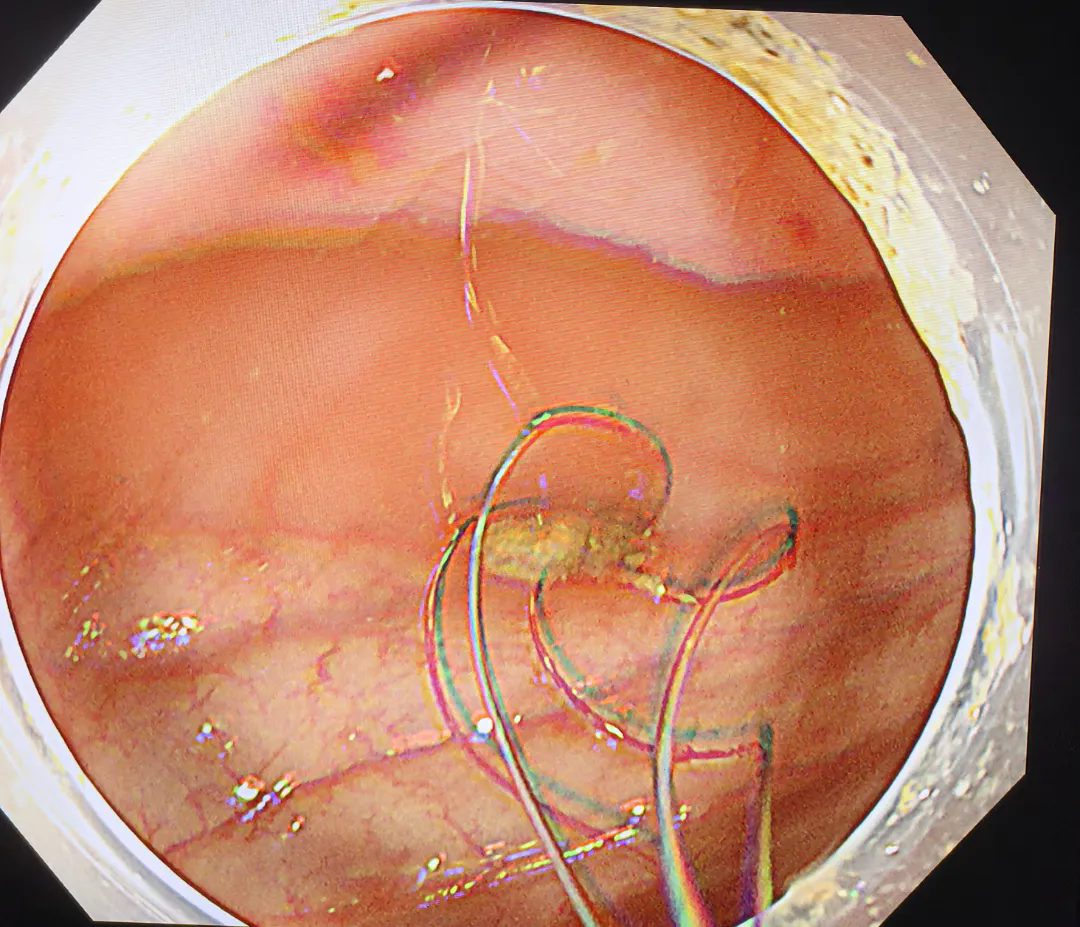

完善術(shù)前相關(guān)準(zhǔn)備,在麻醉科、內(nèi)鏡中心醫(yī)護(hù)人員的全力配合下,由李海菊主任、劉繼威主治醫(yī)師及楊國(guó)帥主治醫(yī)師等人組成的手術(shù)團(tuán)隊(duì)為劉先生實(shí)施了內(nèi)鏡下闌尾糞石取出術(shù)+內(nèi)鏡下逆行闌尾腔沖洗術(shù)+內(nèi)鏡下闌尾支架置入術(shù),術(shù)中通過(guò)沖洗、引流、網(wǎng)籃套取等操作,將嵌頓于闌尾腔內(nèi)的糞石取出,并放置支架一枚引流,術(shù)后患者腹痛明顯緩解,麻醉清醒后即可下地行走并恢復(fù)進(jìn)食。

置入支架